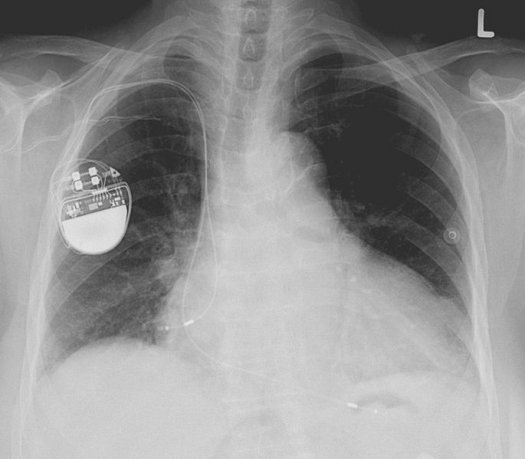

Pacemakers, internal cardiac defibrillators (ICDs) and other prosthetics with electronic components are usually removed, especially in the case of cremation, as they contain batteries that can explode. One 2002 study found that “about half of all crematoria in the UK [United Kingdom] experience pacemaker explosions.” The first reported case of such an explosion, in 1976, created “a finger-sized hole half an inch deep” in the crematorium wall. (Death via crematorium pacemaker explosion would be a bad, and perhaps ironic, way to go.)

There are currently rules against re-using many prosthetics, such as pacemakers, in Europe and the U.S. But these devices cost a lot; some people in the developing world cannot afford new ones. So several charities are trying to reuse these. In the UK, the charity Pace4Life collects and sends working pacemakers to India. An American effort called Project My Heart Your Heart is looking to do the same thing in the U.S., and has found that “75 patients who received second-hand ICDs showed no evidence of infection or malfunction.”